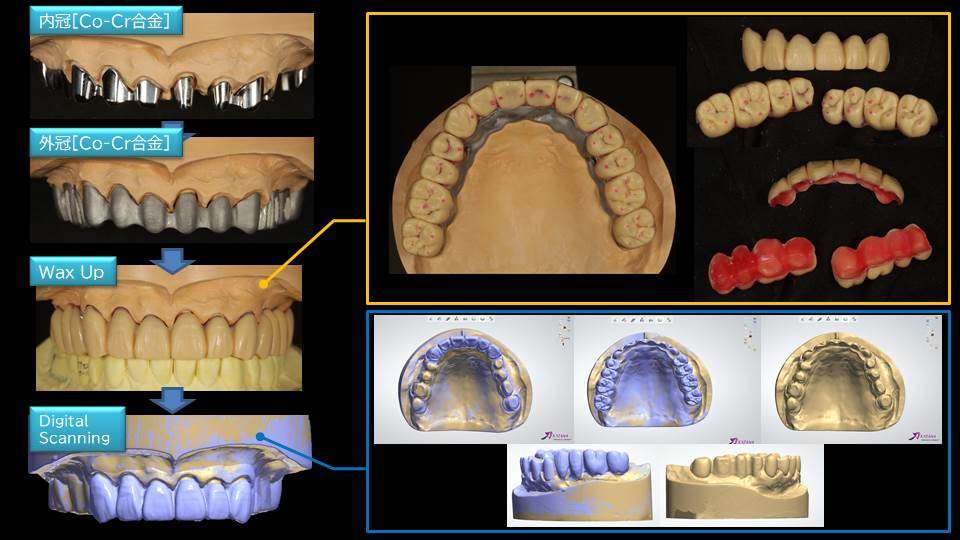

写真は、虫歯や歯周病で歯がボロボロ・グラグラになってしまっても、お仕事も忙しく歯医者に長年通院できず、やっとの思いで当院に受診された患者様です。残念ながら、歯ぎしりや食いしばりで歯が割れている部分や、むし歯が大きすぎてボロボロで残せない歯は抜歯をして、部分的にインプラントを埋入して、テレスコープ義歯とジルコニア セラミックスを用いる最新式の入れ歯の専門治療を計画し、審美性と咀嚼機能の改善を図ることにしました。

最終補綴装置の設計としては「閂(カンヌキ)式の入れ歯」である「リーゲル テレスコープ」で治療させて頂きました。バネ式の入れ歯ではありませんので、一度得られた歯並び、咬み合わせ、装着感には長期に渡って変化がありません。

(テレスコープ義歯:Co-Cr-Mo合金を使用 / インプラント:SPI社 CONTACT を使用)